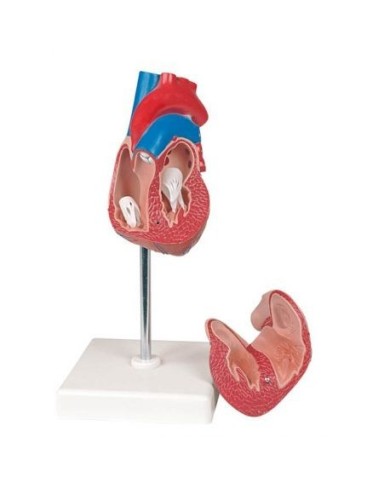

Kit composto da 3 modelli

Su Base, staccabile

Con scheda descrittiva dettagliata

Modello di cuore di alta qualità scomponibile in 5 parti

Modello di cuore di alta qualità scomponibile in 5 parti

La parete anteriore del cuore è staccabile per poter vedere i ventricoli.